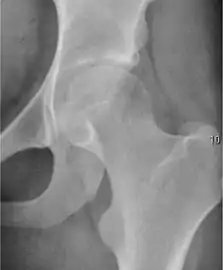

Projectional radiography ("X-ray") is the first imaging technique of choice in hip pain, not only in older people with suspected osteoarthritis but also in young people without any such suspicion. In this case plain radiography allows categorization as normal hip or dysplastic hip, or with impingement signs, pincer, cam, or a combination of both.[1]

Projectional radiography ("X-ray") is currently useful not only in older people in whom osteoarthritis of the hip is suspected but also in younger people without osteoarthritis, who are being evaluated for femoroacetabular impingement (FAI) or hip dysplasia.[1]

Plain radiography allows us to categorize the hip as normal or dysplastic or with impingement signs (pincer, cam, or a combination of both). Besides these, pathologic processes like osteoarthritis, inflammatory diseases, infection, or tumors can also be identified (Figure 1).[1]